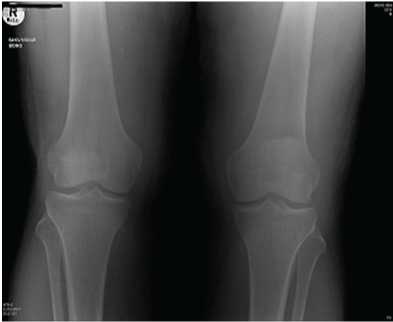

A 53 year-old male presented with history of fall down over his flexed knees while descending from stairs and complaining of bilateral knee pain, swelling and inability to bear weight. He is known to have chronic renal failure secondary to membranous glomerulonephritis for the last 15 years. He is on hemodialysis three times per week since that time. He has history of two rejected renal transplant in the last seven years. Clinical examination revealed bilateral severe effusion around the knee with tenderness to palpation. A palpable left infrapatellar and right suprapatellar gaps are detected. His knees were in 20-30 degrees of flexion with restricted active flexion due to pain and effusion. He has bilateral loss of extensor mechanism. Bilateral knee x-rays showed left knee patella alta with Insall-Salvati ratio of 0.48. Right knee x-ray showed no obvious abnormality with Insall-Salvati ratio of 1.07 (Figure 1–3).

Figure 1 Bilateral knee AP radiograph at the time of injury.